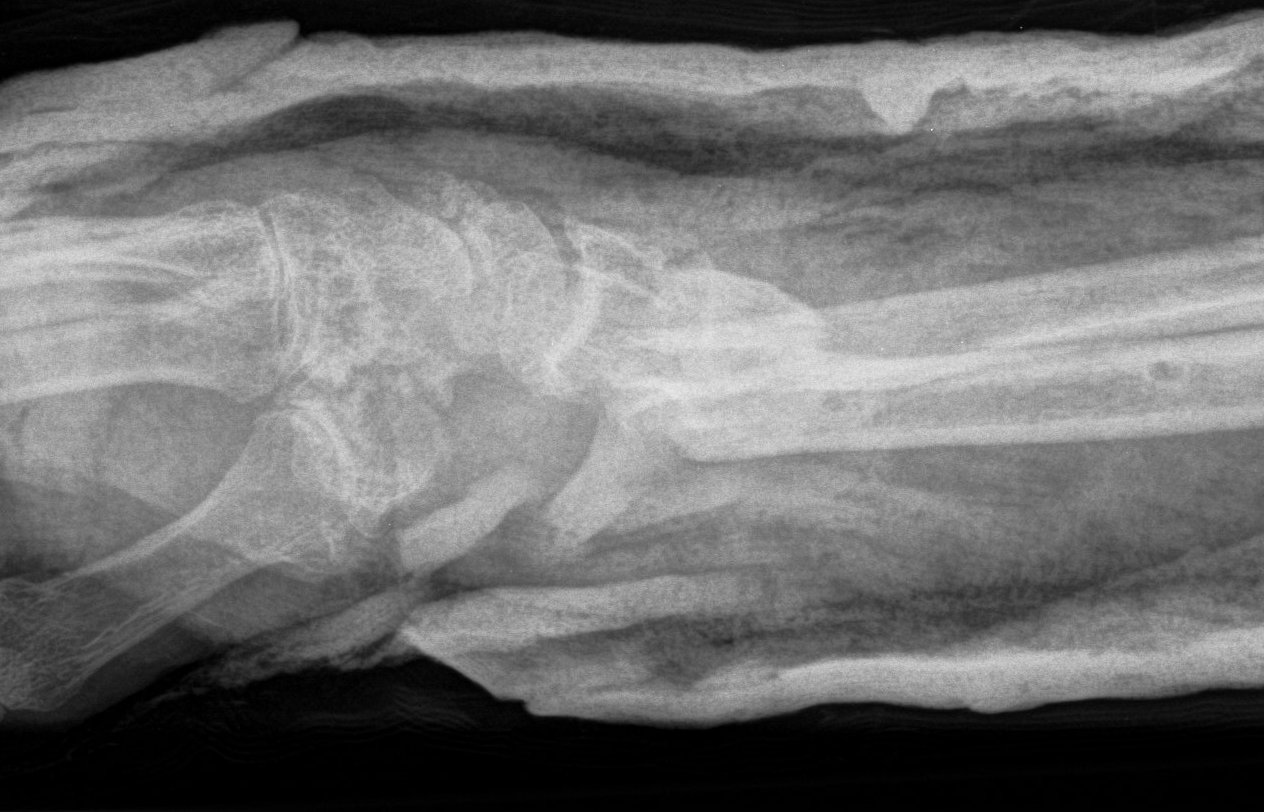

Dr shortDR short

Distal radius fracture with shortening and dorsal tilt